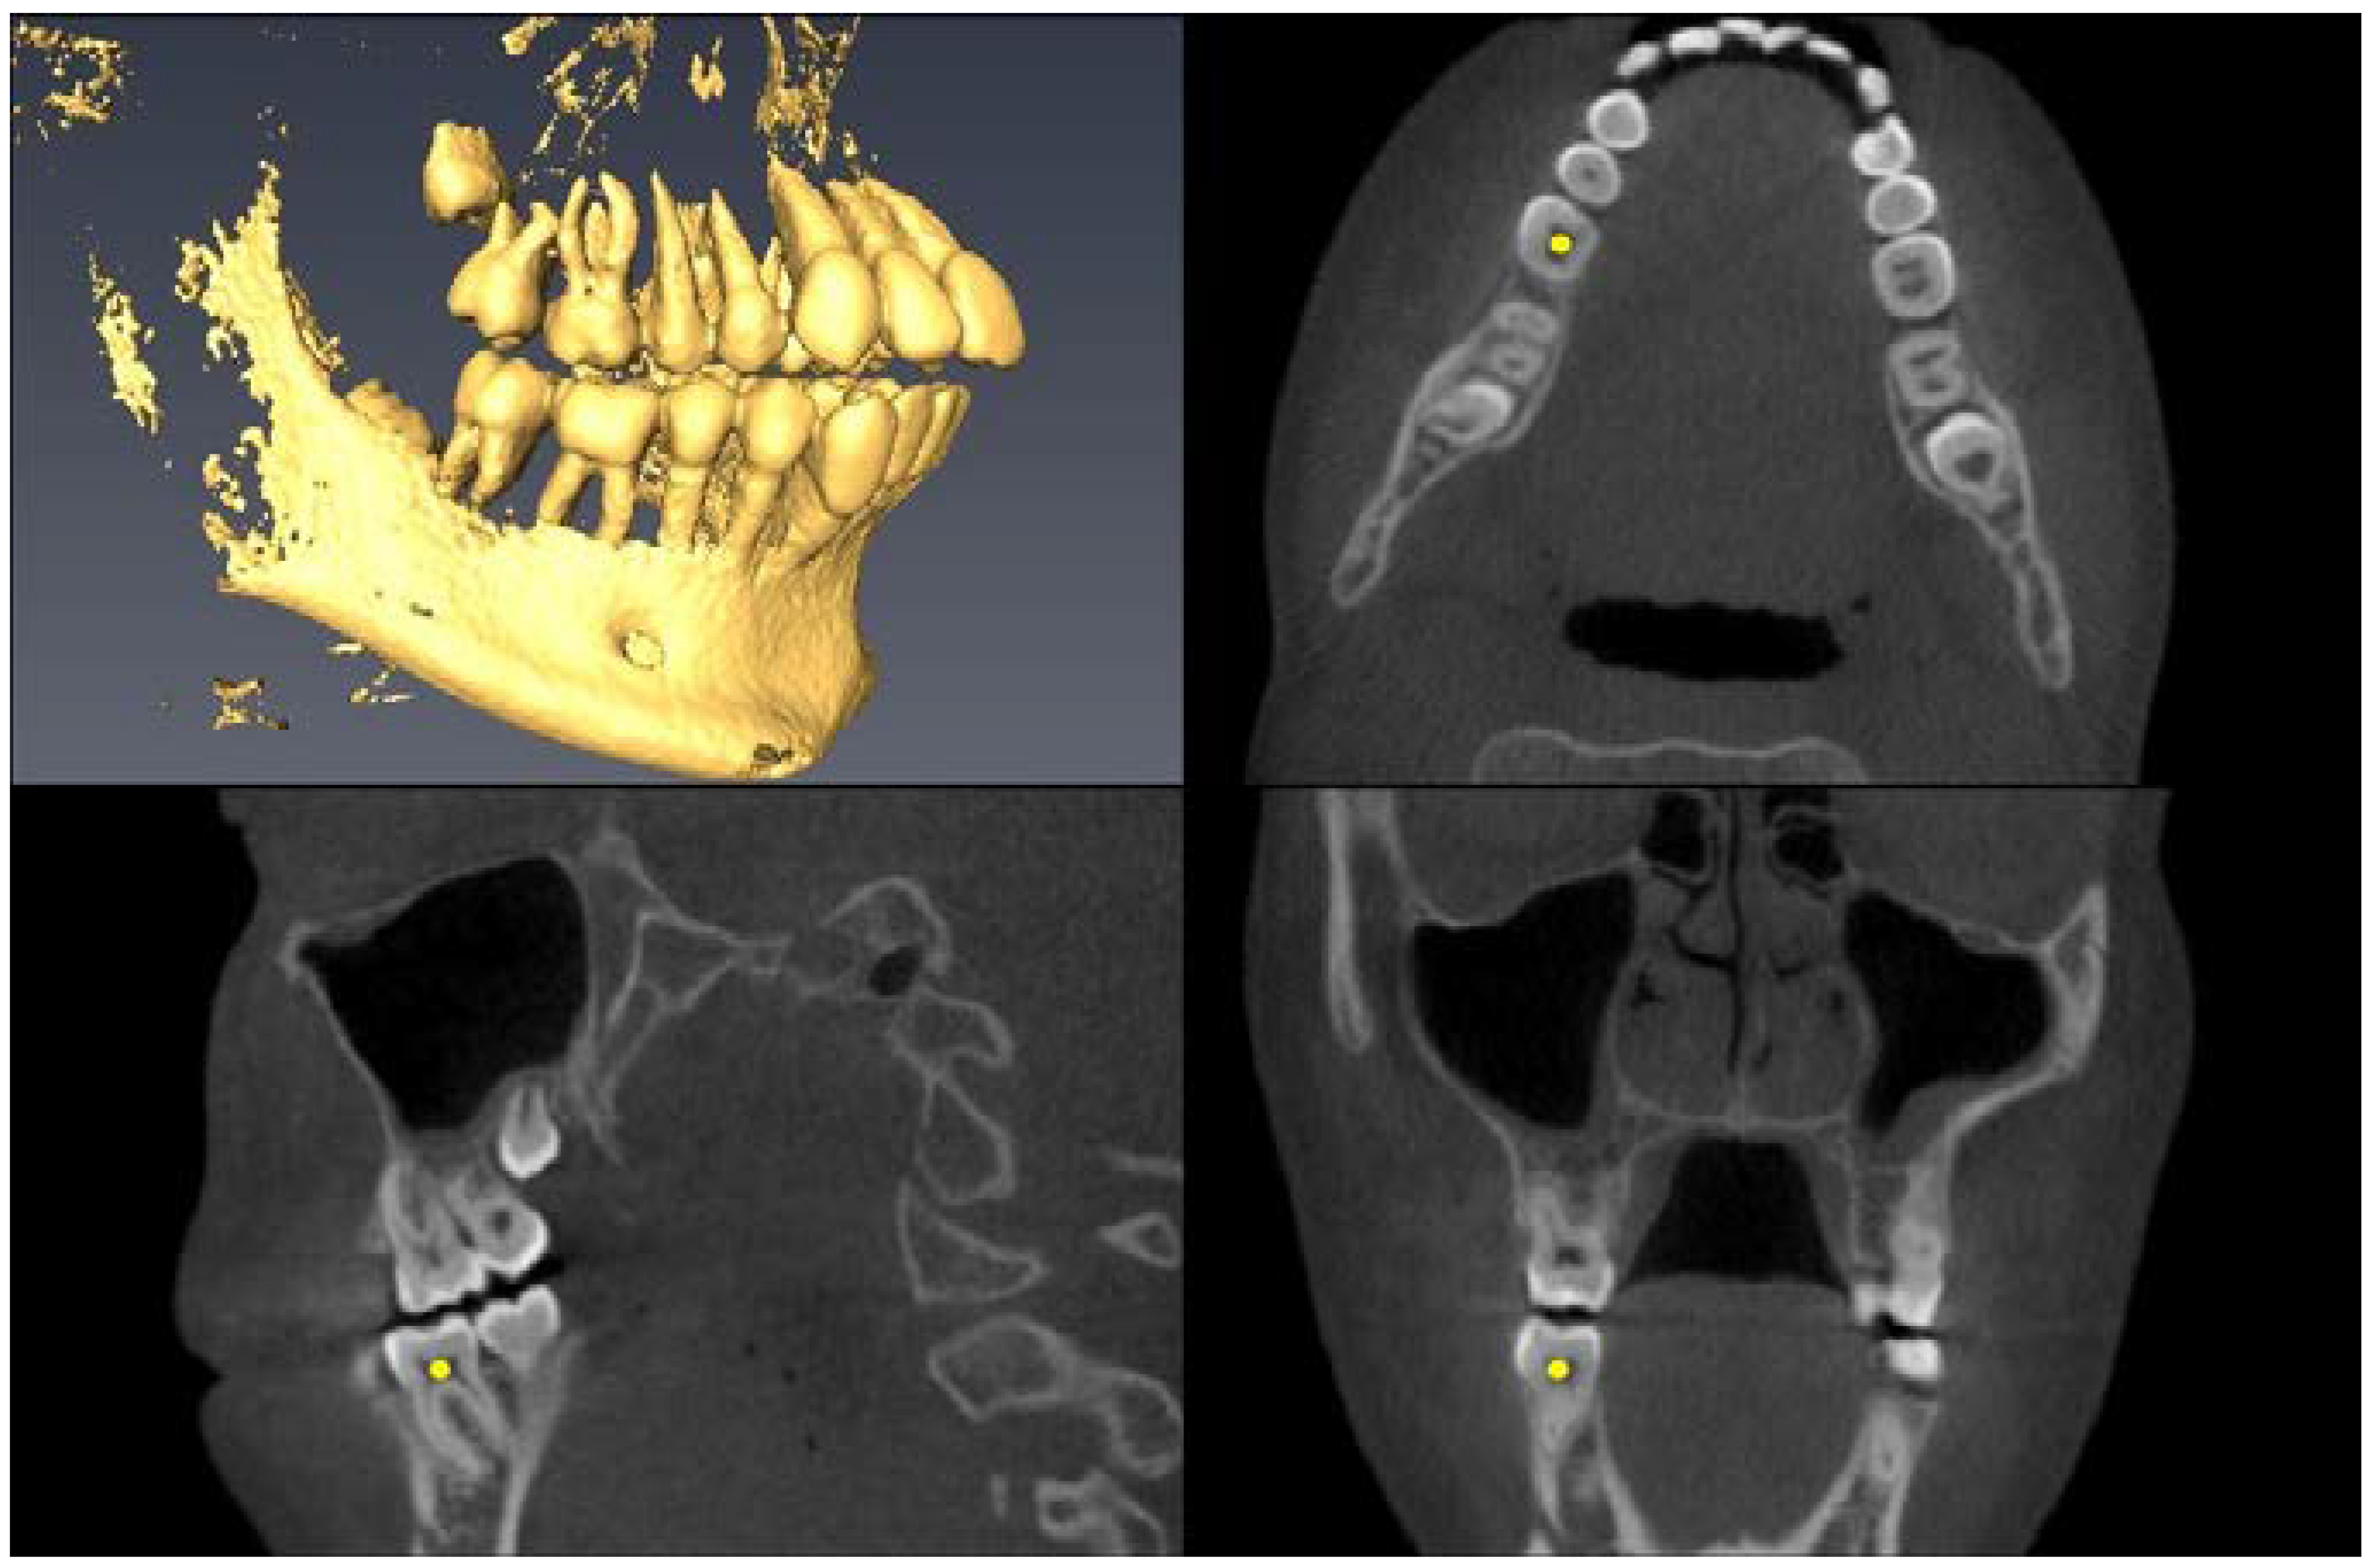

| Landmark Description | 3D View (Upper Left), Axial View (Upper Right), Sagittal View (Lower Left), Coronal View (Lower Right) |

| Upper First Molar Alveolar Bone =alveolar bone next to mesial root apex | ![]() |